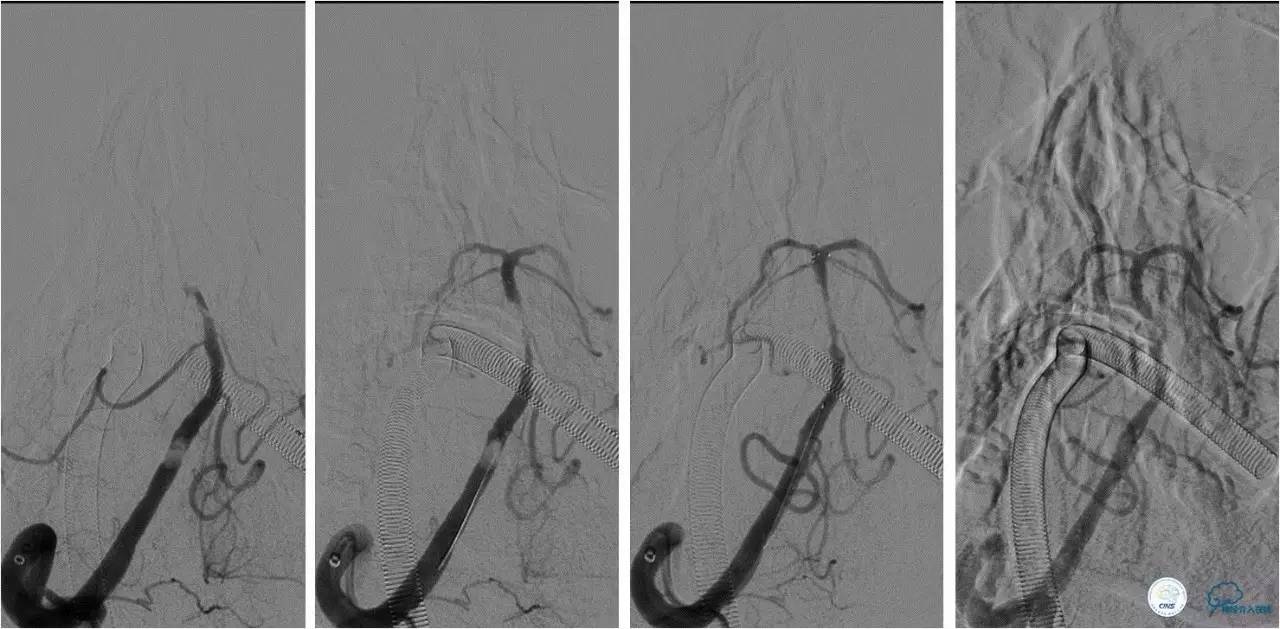

》术中造影

★右侧椎动脉起始端长段闭塞,右侧颈深动脉向右侧椎动脉供血,远端基底动脉不显影;左侧椎动脉纤细,V3段以远不显影。

★右侧颈总动脉正侧位,可见右侧枕动脉通过肌支向右侧椎动脉供血,远端基底动脉不显影。

》治疗过程

★2.0x20 mm球囊扩张后,右椎动脉起始段见前向血流,将6F navien颅内支撑导管送至V3段造影,见V4段有血栓,基底动脉闭塞 ;

★Solitaire 6.0x20 mm取栓支架到位造影,取栓两次后基底动脉再通。

★取栓后处理椎动脉起始端的狭窄,椎动脉开口处先放置一枚球扩支架,造影见支架远端仍有狭窄,将Solitaire 6.0x20 mm贴敷在狭窄段,造影见前向血流改善(TICI分级 3级)。